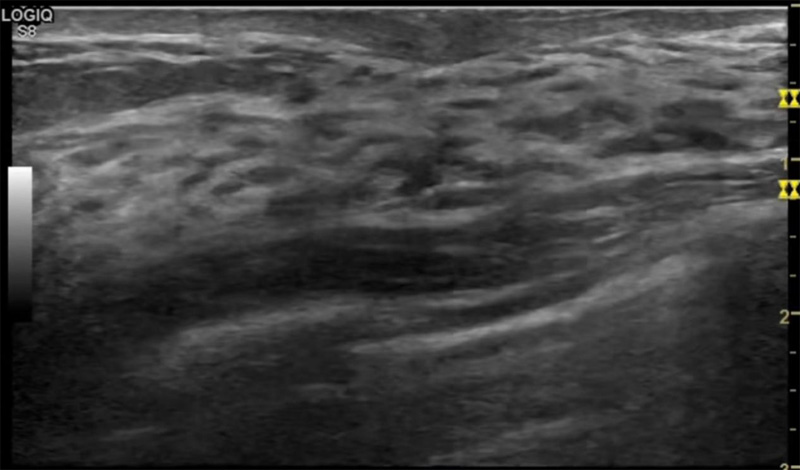

乳房脹痛,觸摸疼痛,手摸起來感覺有腫塊。這個是什么問題呢?醫生診斷一般是乳腺增生。那么在乳腺超聲設備檢查后,報告單卻顯示雙乳未見明顯占位性病變。乳腺增生是很多女性,特別是育齡期女性都有的經歷、到底乳腺增生癥狀有哪些?會給我們帶來怎樣的影響呢?乳腺增生不是腫瘤跟炎癥。乳腺組織增生及退行性變跟內分泌功能紊亂有關系。正常的生理改變。還有乳腺病,良性乳腺結構不良等名稱。

乳腺增生有什么癥狀,病因?比較典型的就是乳房疼痛,特別是經前癥狀比較重,經后就有所緩解。有時候還能碰到乳房硬塊。根據經期的變化而變化硬度大小都有變。乳腺在內分泌激素,伴隨月經周期有增生問題。內分泌激素代謝失衡,雌激素水平增高,出現乳腺組織增生過度,增生組織不退的情況下,就會有乳腺增生癥狀。這個不會增加乳腺癌的風險。所以不用緊張的。不過乳腺癌的病人都會有乳腺增生。所以乳腺增長有沒癥狀,都需要進行常規的體檢。